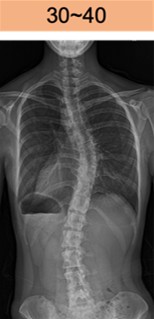

コブ角 30-40度

30°~40°